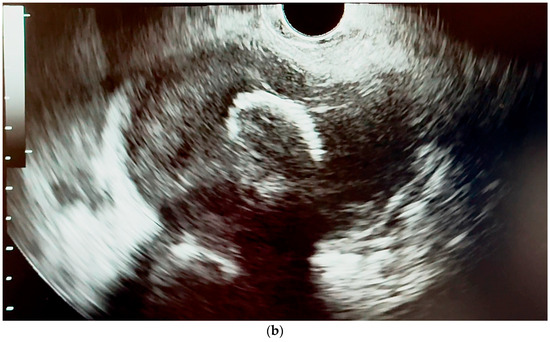

6.4.1. Endoscopic Ultrasound (EUS)